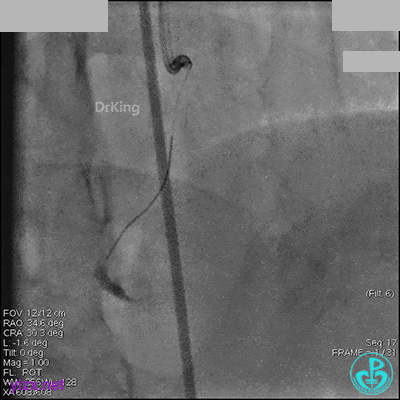

右冠脉中段充分扩张后欲植入3.5×38mm支架时,支架难以通过中远段扭曲处,且指引导管、导丝弹出飞扬。反复尝试导丝重新到达右冠脉远端时通过不顺利,局部造影剂滞留,远端血流接近3级。

右冠脉血流3级,患者无症状,终止手术。